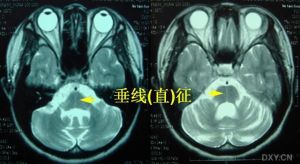

(4)輔助檢查:①X片可見脊柱和骨骼畸形;MRI可見脊髓變細;②心電圖常見T波倒置、心律失常和傳導阻滯,超聲心動圖示心室肥大,視覺誘發電位波幅下降;③DNA分析FRDA基因18號內含子GAA大於66次重複。

遺傳性共濟失調2、Friedreich型共濟失調(FRDA)X片可見脊柱和骨骼畸形;MRI可見脊髓變細;心電圖常見T波倒置、心律失常和傳導阻滯,超聲心動圖示心室肥大,視覺誘發電位波幅下降。